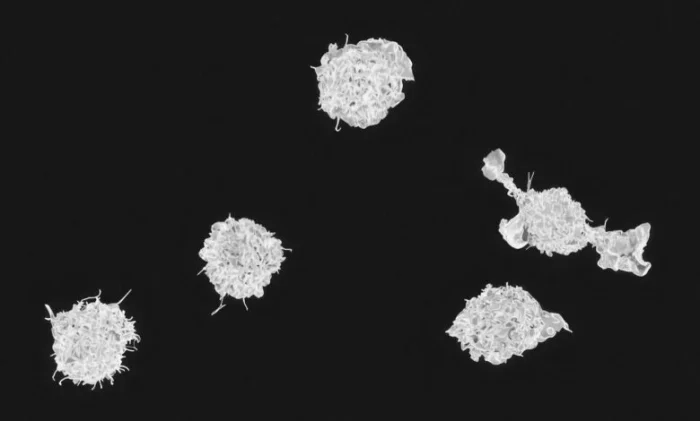

Система комплемента состоит примерно из 50 различных белков, которые циркулируют в крови и тканях в неактивном состоянии. Когда организм обнаруживает угрозу, например, бактерии, проникающие в рану, эти белки активируются в строгой последовательности, подобно падающим костяшкам домино.

Действуя как хорошо организованная армия, белки комплемента помечают патогены для уничтожения, привлекают другие иммунные клетки к месту инфекции и даже разрушают мембраны вредоносных микробов. Этот каскад реакций помогает предотвратить распространение инфекции в организме.

Ученые выяснили, что система работает по принципу «порога перколяции». Это означает, что белки комплемента запускают полноценный иммунный ответ только тогда, когда их достаточно много и они плотно расположены на поверхности чужеродного объекта — будь то бактериальная клетка, наночастица вакцины или медицинский имплантат. Если белки находятся слишком далеко друг от друга, иммунный ответ затухает. Но если их концентрация достигает критического уровня, активация происходит стремительно.